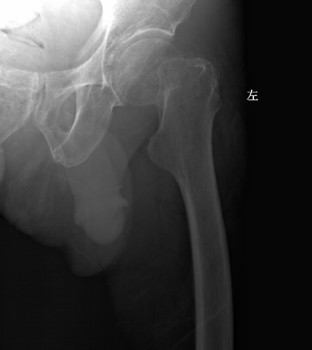

一般情况介绍 患者张XX,男,69岁,因“跌倒致左髋疼痛、活动障碍6天”入院。既往史:“糖尿病”15年,一直服“拜糖平”、“二甲双胍”治疗,血糖控制在 7~15mmol/L之间。高血压病史4年,最高达180/90mmHg,未系统服药治疗。曾有脑梗塞病史,2月前因“双侧颈动脉粥样硬化、右颈内动脉中 度狭窄”行右颈动脉支架成形术,现服用波立维、拜阿斯匹林联合抗血小板治疗。查体:左髋部无肿胀、瘀斑,关节活动受限,叩痛、压痛(+),左下肢外旋 60°畸形。双足多处皮肤破溃坏死,创面干燥,右足足背动脉搏动不明显。影像学资料:骨盆正位、左侧髋关节侧位示“1、左侧股骨颈骨折;2、骨盆骨质疏 松”(图1、2)。颈动脉超声示“双侧颈动脉粥样硬化伴多发斑块”(图3)。下肢动脉彩超示“双下肢动脉粥样硬化闭塞症声像;右侧胫前及左侧胫前、足背、 胫后动脉广泛狭窄(中-重度);右足背动脉狭窄(轻度)” (图4)。下肢静脉彩超示“左下肢深静脉血栓栓塞声像:左侧腓静脉(后一条)及左小腿多发肌间静脉完全栓塞。双侧股静脉及腘静脉血流缓慢。余双下肢深静脉 及大隐静脉近段未见明显异常声像” (图5)。心脏彩超示“主动脉硬化、主动脉瓣退行性变;左房增大,心内血流未见明显异常;左室收缩功能未见异常,舒张功能减退”。血生化指标:凝血四项示 “纤维蛋白原6.64g/L”,D-二聚体“1499ng/ml”。结合患者病史、体征及辅助检查,诊断“1、左股骨颈骨折;2、Ⅱ型糖尿病;3、高血压 病;4、脑梗塞后遗症;5、右颈动脉支架成形术后”。请内分泌科、心血管内科会诊,停用波立维、拜阿斯匹林,行降糖、降压、营养支持等对症治疗。入院后两 周在气管插管全麻下行“左侧人工股骨头置换术”,术程顺利。患者麻醉清醒后即嘱其行双下肢肌肉主动舒缩及膝踝关节屈伸活动,术后12h开始首次应用磺达肝 癸钠2.5mg皮下注射,以后每天以同等剂量皮下注射一次。患者术后5天即可在助行器帮助下下床活动,磺达肝癸钠持续用至10天停止,并防治感染、降糖、 降压、营养支持治疗。治疗期间每日观察患肢是否有肿胀情况,测量双侧大腿及小腿周径并记录。术后两周复查双下肢动静脉彩超,与术前结果相同;行肺部X线片 及CT检查,未见肺动脉栓塞征象。骨盆X线片示人工股骨头置换术后改变,人工假体位置佳(图6)。患者顺利出院,并恢复波立维、拜阿斯匹林联合抗血小板治 疗。

图2 术前左髋侧位片